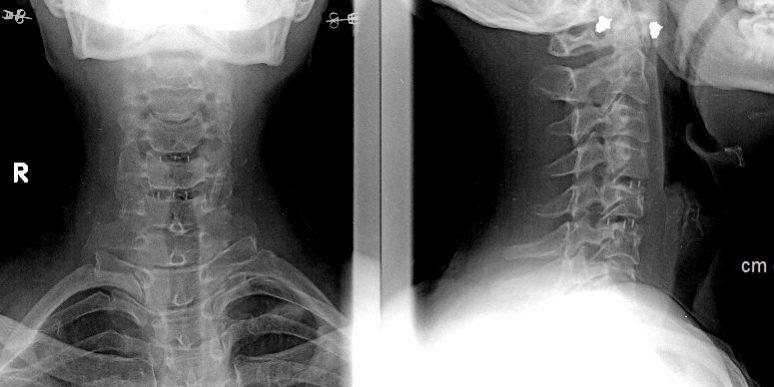

Ασθενής γυναίκα 60 ετών με άλγος αυχένα και αριστερού άνω άκρου (κατανομής κυρίως Α6 και λιγότερο Α5 ρίζας). Συντηρητική αγωγή με φυσικοθεραπεία, παυσίπονα και κορτικοειδή δεν είχαν οδηγήσει σε σημαντική ανακούφιση από τα συμπτώματα.

Ο απεικονιστικός έλεγχος με μαγνητική και αξονική τομογραφία της σπονδυλικής στήλης ανέδειξε εικόνα δισκοκήλης στα επίπεδα Α5/6 και λιγότερο Α4/5. Το σημαντικότερο εύρημα ήταν η πλάγια τρηματική στένωση με πίεση επί των ριζών Α6 & Α5 αριστερά.